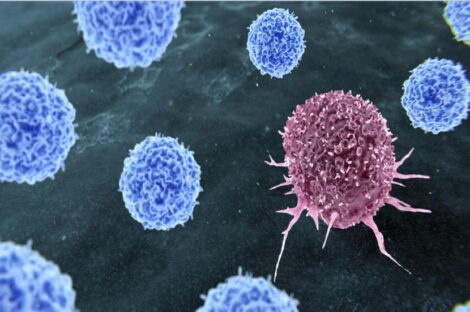

تطور طبي يوصف بالاختراق الثوري، حيث أعلن باحثون من جامعة رايس في تكساس عن تطوير علاج جديد للسرطان يعتمد على…

كشفت دراسة حديثة أجراها مركز أبحاث السرطان في جامعة فيينا الطبية عن اختراق علمي محتمل قد يغيّر جذرياً الطريقة التي…

شهد المجال الطبي تطورًا ملحوظًا مع الإعلان عن علاج مناعي مبتكر لمرضى سرطان الرأس والرقبة، والذي أظهر نتائج واعدة في…